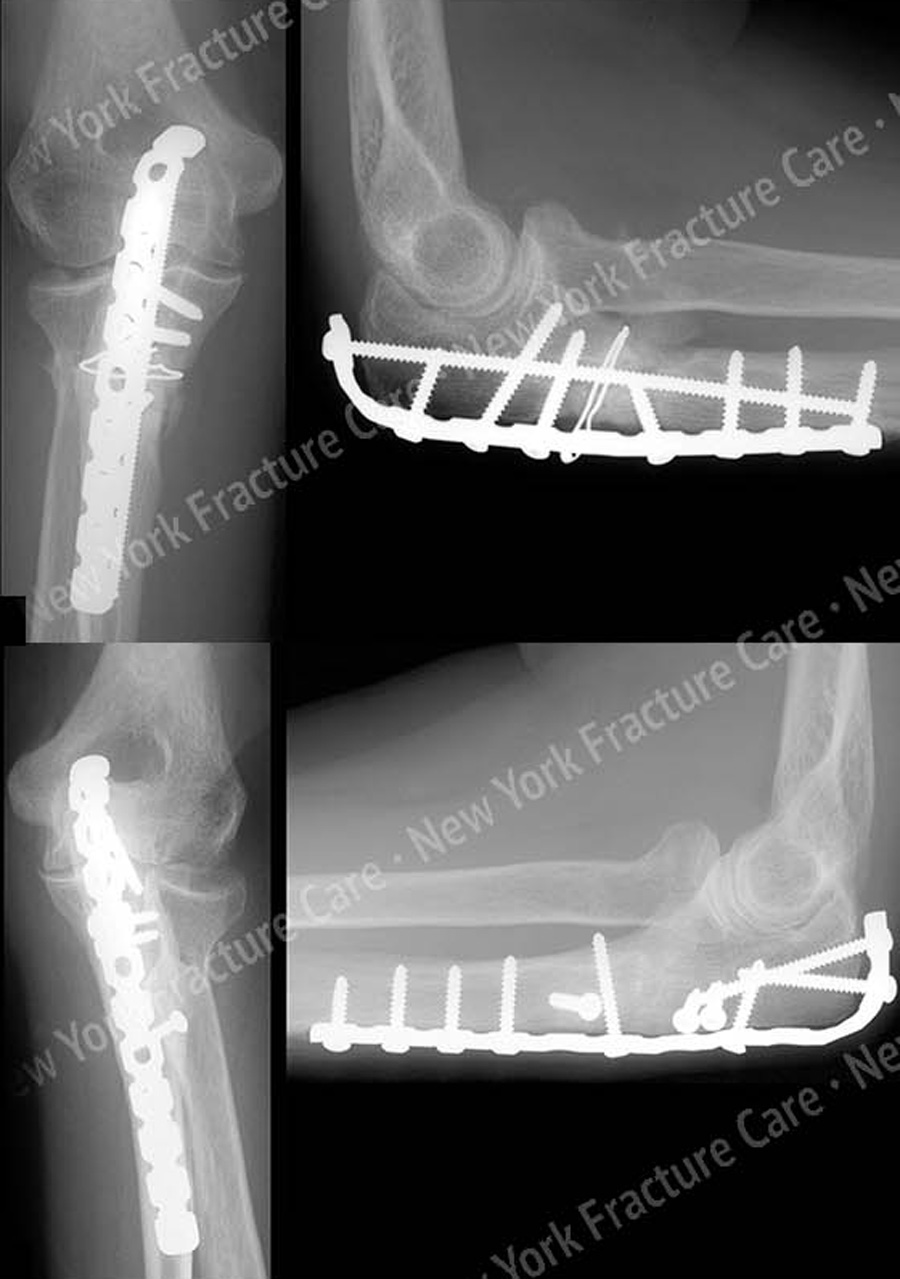

Медицинские снимки: Пластина в левом предплечье